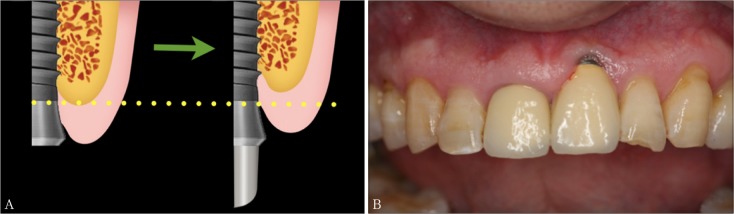

即刻种植是在上颌前牙区拔牙后的牙槽窝里立即植入种植体,并且位于天然牙根偏腭侧的骨组织里[7],此时植入超出牙槽窝上方约3~5 mm的种植体部分的外形结构就决定了该种植体的初期稳定性,即种植体根方的外形设计决定了其初期稳定性,种植体其余部分因位于新鲜牙槽窝内只接触到少量的牙槽骨,基本无助于获取初期稳定性(图1)。而种植体根方外形设计主要体现在种植体轮廓设计、螺纹设计及自攻性方面。目前种植体轮廓设计主要可分为锥形种植体和柱形种植体。现有体外实验证明,锥形种植体在植入时可对周围骨组织产生侧向压力,种植体螺纹与骨组织更加紧贴,植入扭矩较高,有利于增加初期稳定性[8]–[9]。Kan等[10]回顾了112名患者前牙美学区进行的即刻种植手术,发现锥形种植体比柱形种植体更容易在即刻种植手术中获得良好的初期稳定性,并且锥形种植体的根方缩窄,更适合应用于骨量局限的即刻种植手术中。种植体表面螺纹的设计是为了方便种植体就位,增加骨结合面积,提高初期稳定性,产生有利的应力分布从而使骨组织保持稳定[11]。因此,种植体根方螺纹深而密集的种植体更有利于增加种植体与拔牙窝上方仅有的3~5 mm的骨组织的接触面积以获得良好初期稳定性。此外,种植体根尖1/3带有切割刃设计的种植体可具有良好的自攻性[9],可允许极差备洞的方式植入种植体,种植体在植入过程中可以逐步挤压周围骨质,使种植体在骨质条件较差情况下依然获得良好的初期稳定性[12]。Kan等[10]的研究表明,在即刻种植手术中,种植体与终末钻的直径相差0.5 mm以上组的种植体初期稳定性显著高于直径差小于0.5 mm组。即刻种植手术中,自攻性良好的种植体可以在极差较大的备洞条件下顺利植入,取得良好的初期稳定性,且避免植入过程的过度产热从而影响骨结合[9]。基于现有文献及笔者多年临床体会,具有良好自攻性及密集深螺纹的锥形种植体有利于提高即刻种植的初期稳定性,也直接关系到即刻修复能否顺利进行。北京大学口腔医院种植科于1996年开展即刻种植以来,取得了令人满意的临床效果,患者的手术创伤、就诊次数减少,种植体的长度及轴向理想,长期成功率类似于常规种植,患者满意度高[13]。

图 1. 种植体根方3~5 mm的外形设计影响了种植体初期稳定性的获得.

Fig 1 Apical 3-5 mm profile design of implant determines the preliminary stability

A:上颌前牙即刻种植时的种植体三维位置示意图;B:种植体根方超出牙根3~5 mm是获得初期稳定性关键部分;C:不同设计的种植体,其根方形态设计即红色线条以上部分可能影响了即刻种植时初期稳定性。